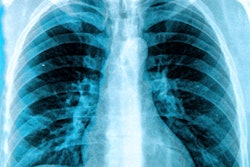

Almost 60% of chest x-rays taken in urgent care settings in patients with confirmed and symptomatic COVID-19 are interpreted as "normal," according to a study to be published in the May issue of the Journal of Urgent Care Medicine (JUCM).

The findings suggest that, in the absence of confirmation of disease via reverse transcription polymerase chain reaction (RT-PCR) testing, ambulatory care clinicians should be cautious when a chest x-ray is interpreted as negative if a patient is demonstrating signs of COVID-19, wrote a team led by Dr. Michael Weinstock of Ohio State University in Columbus and senior editor of JUCM.

Most patients with COVID-19 have mild respiratory symptoms, and many are first seen in nonemergency and nonhospital settings, such as urgent care centers. Chest x-ray is often the first imaging exam acquired after a positive RT-PCR if a patient is at risk for disease progression, Weinstock's group said.

To assess what percentage of patients with confirmed disease would have normal versus abnormal chest x-rays, the researchers conducted a study that included 636 patients with positive RT-PCR tests for the SARS-CoV-2 virus who underwent chest x-ray between March 9 and March 24.

Patients were identified via electronic medical records taken from an urgent care network of 100 centers in New York and New Jersey. The group sought to determine how many of these patients had normal versus abnormal x-rays. A secondary goal was to describe typical COVID-19 abnormal findings on chest x-ray.

The group found that almost 90% of COVID-19-positive patients had either normal or mildly abnormal chest x-rays, despite having respiratory symptoms of the disease. Effusions and lymphadenopathy were rare. The authors also found the following:

| Characteristics of chest x-ray in patients with confirmed COVID-19 | |

| Imaging characteristics | Percentage of total patients |

| Severity | |

| Normal | 58.3% |

| Mild | 30.7% |

| Moderate | 10.2% |

| Severe | 0.8% |

| Abnormal finding | |

| Interstitial | 23.7% |

| Ground-glass opacities | 18.9% |

| Consolidation | 5.3% |

| Location | |

| Lower | 33.8% |

| Upper | 20.1% |

| Diffuse | 0.9% |

"The majority of COVID-19 patients who present in [the urgent care] setting show no identifiable abnormalities on standard chest x-ray assessment," the team wrote.